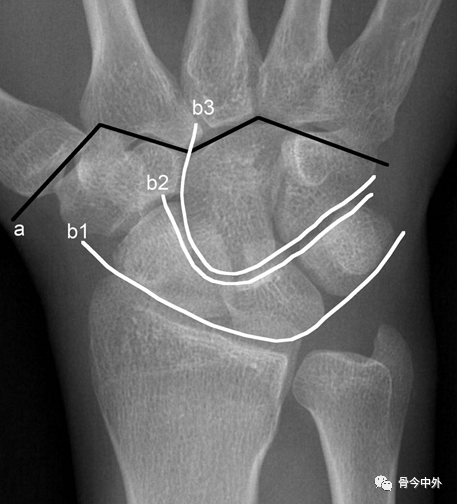

图11 a. M形腕掌线 b.腕骨弧线(Gilula线)

若显示腕骨弧线不连续或各弧线不平行,或腕掌线M形结构消失,应高度怀疑腕关节不稳或脱位。

Gilula 提出三个平滑的弧形勾画出近侧列和远侧列腕骨。弧 I 把舟骨、月骨和三角骨近端关节面连在一起;弧 Ⅱ 勾画出上述骨远端凹面;弧 Ⅲ 由头状骨和钩骨远端凸面所形成。

图16腕骨弧。在正常腕关节背掌位X线片上3个平滑的弧线勾画出近侧列和远侧列腕骨。